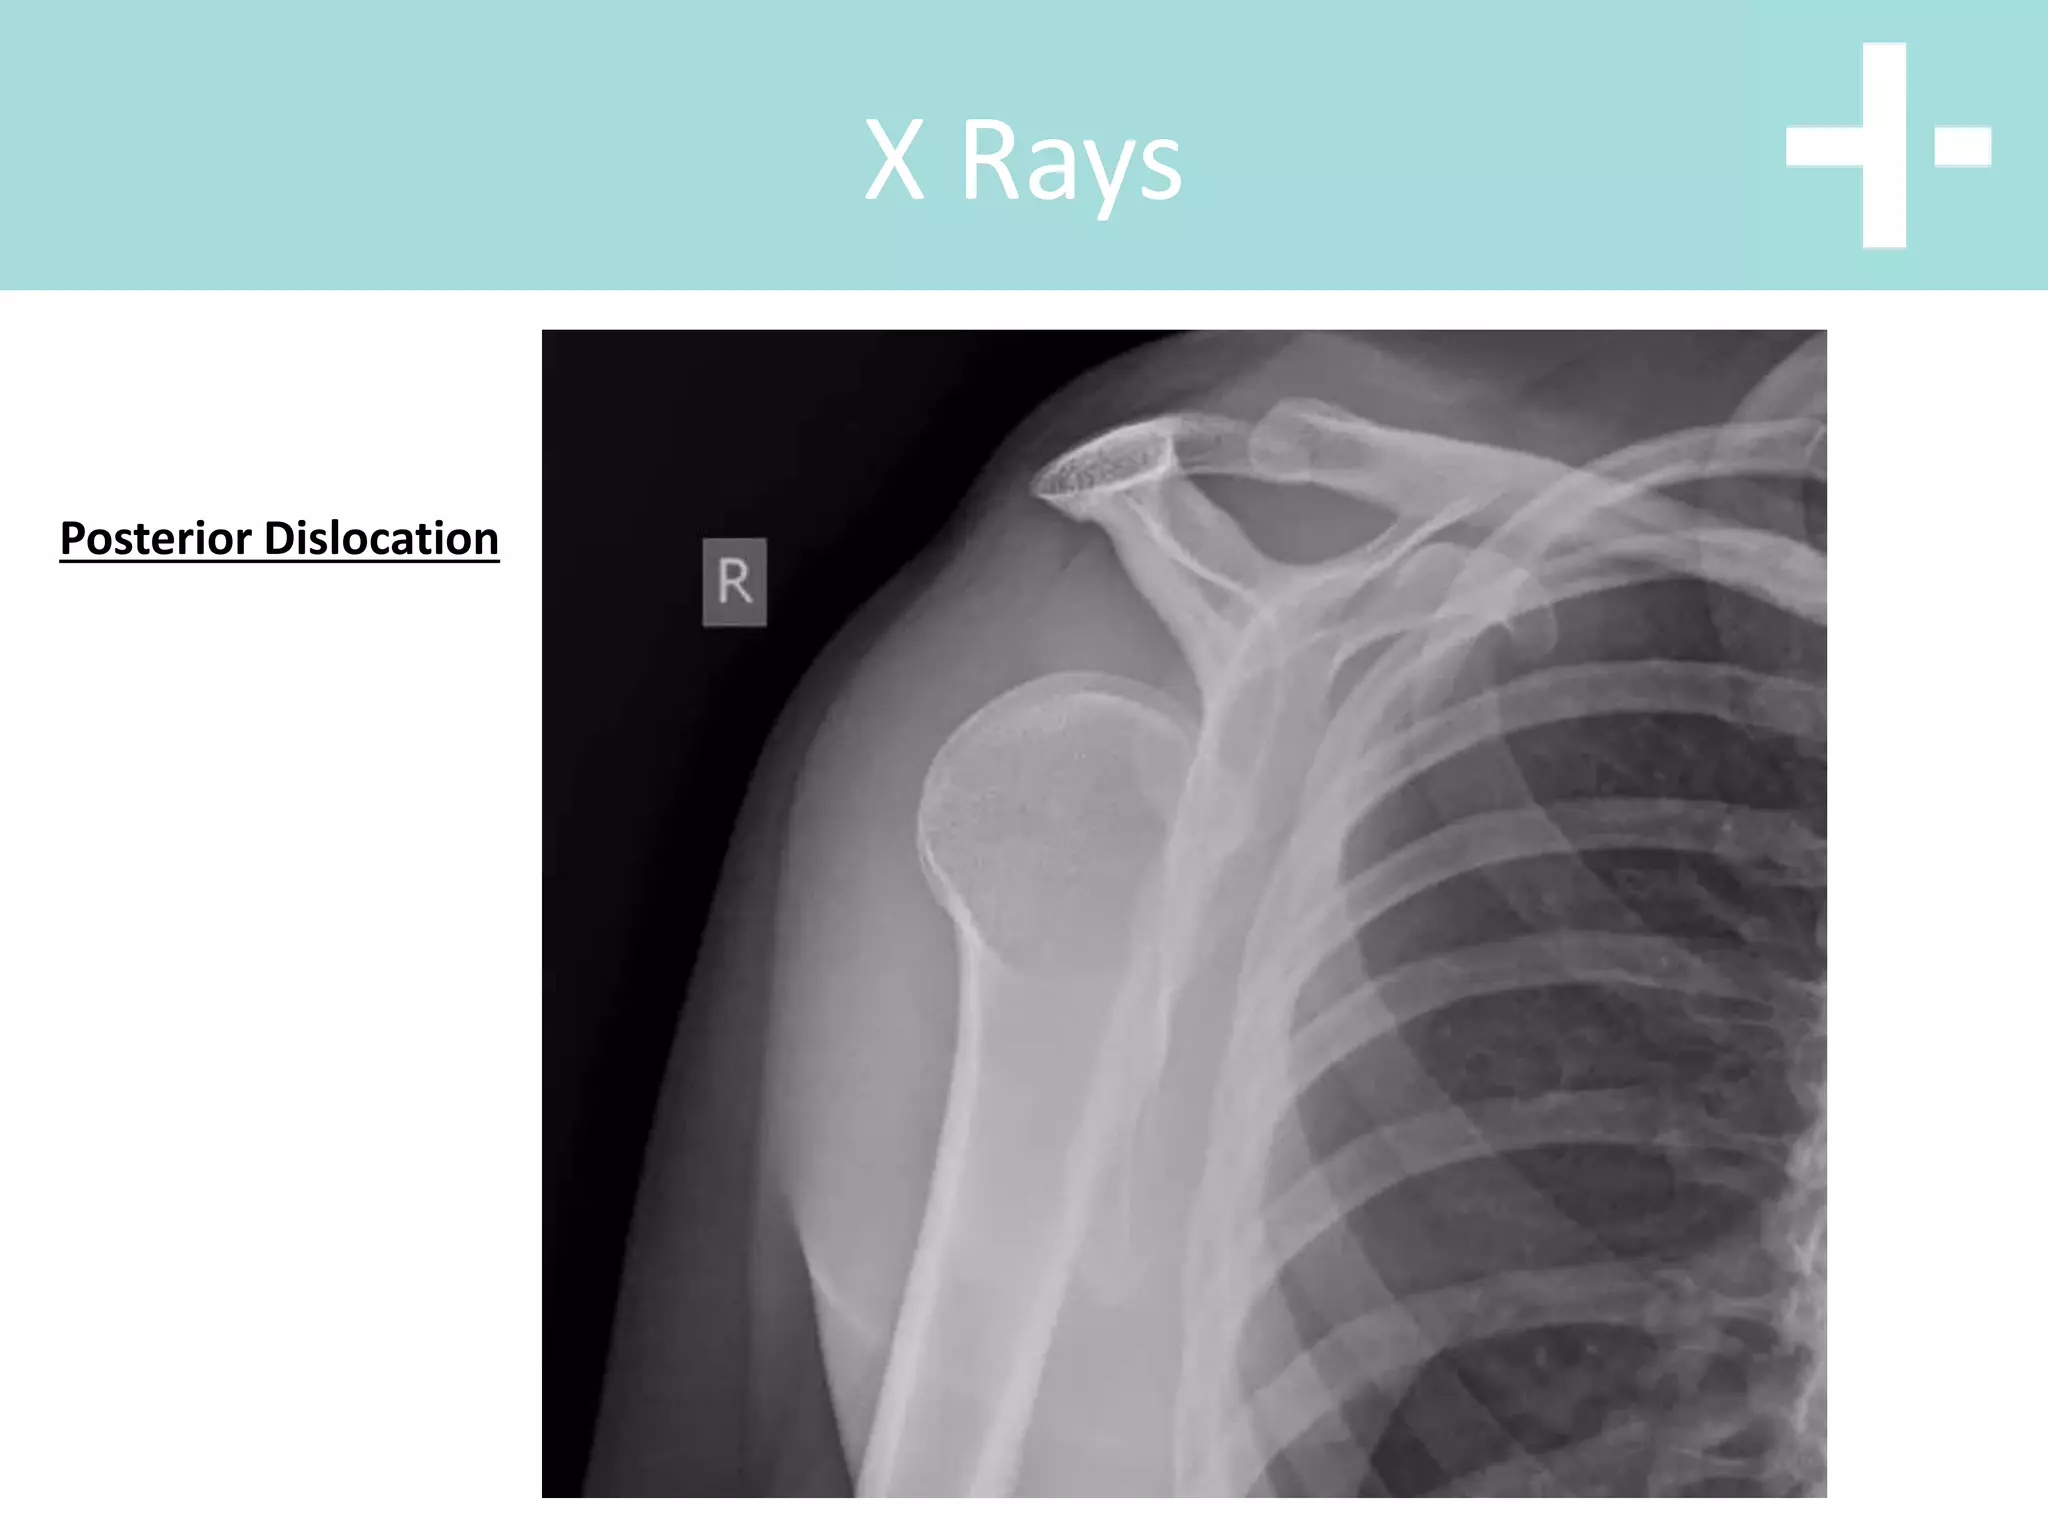

Posterior Dislocation